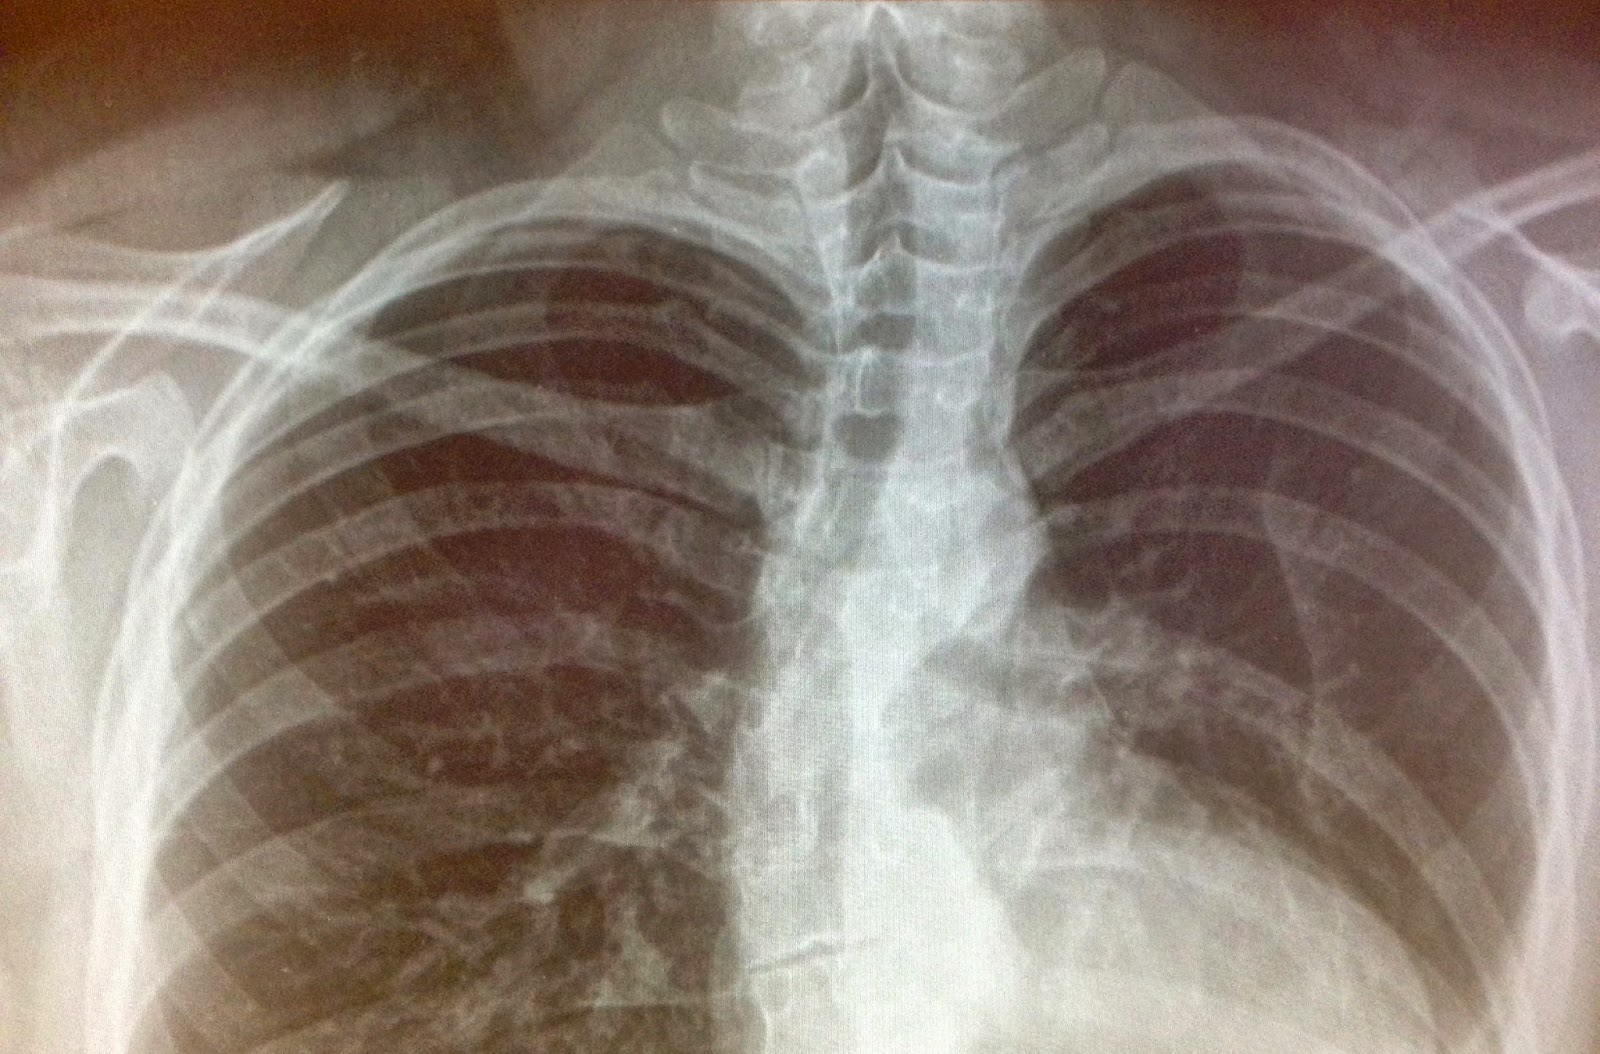

Our orthopedic doctor is always fun to visit. His partner (an orthopedic “fellow”) was also there. He talked to us first and I asked him to demonstrate on a model of the spine just what they did. That was helpful. The two incisions are so interesting – we asked him just exactly how that worked. At one point all four surgeons were working simultaneously. Two working through the back incision and two working through the side. Ouch! He said it is certainly the most cool surgery he has ever seen. At this moment our main surgeon walked in. I told him that we were discussing how awesome the surgery had been. He said it was absolutely a very cool surgery! He pulled up the chest X-ray. Wow.. – look for the part of the spine that looks like a bite has been taken out of it. Ouch!